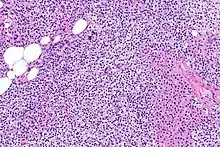

Parathyroid glands are normally composed of chief cells, adipocytes and scattered oxyphil cells.[27][14] Chief cells are thought to be responsible for the production, storage and secretion of parathyroid hormone. These cells appear light and dark with a prominent Golgi body and endoplasmic reticulum. In electron micrographs, secretory vesicles can be seen in and around the Golgi and at the cell membrane. These cells also contain prominent cytoplasmic adipose.[27][14] Upon onset of hyperplasia these cells are described as having a nodular pattern with enlargement of protein synthesis machinery such as the endoplasmic reticulum and Golgi. Increased secretory vesicles are seen and decreased intercellular fat is characteristic.[27][24] Oxyphil cells also appear hyperplasic however, these cells are much less prominent.

Biochemically, there are changes in function between normal and nodular hyperplastic parathyroid glands. These changes involve proto-oncogene expression and activation of proliferative pathways while inactivating apoptotic pathways.[28] In nodular parathyroid tissue increased expression of TGF-a, a growth factor, and EGFR, its receptor, results in aggressive proliferation and further downregulation of vitamin D receptors, which act to suppress hormone secretions.[25][8][28] Furthermore, the proliferative marker, Ki67 is seen to be highly expressed in the secondary nodular hyperplastic state.[28][25] Tumour suppressor genes have also been highlighted as being silenced or degraded in nodular hyperplastic parathyroid tissue.[8][28] One such gene, p53, has been shown to regulate multiple tumour suppressor pathways and in tumorigenesis can be degraded by b-catenin. This pathway, in some aspect, is mediated by CACYBP, which is highly expressed in nodular parathyroid hyperplasia.[28]